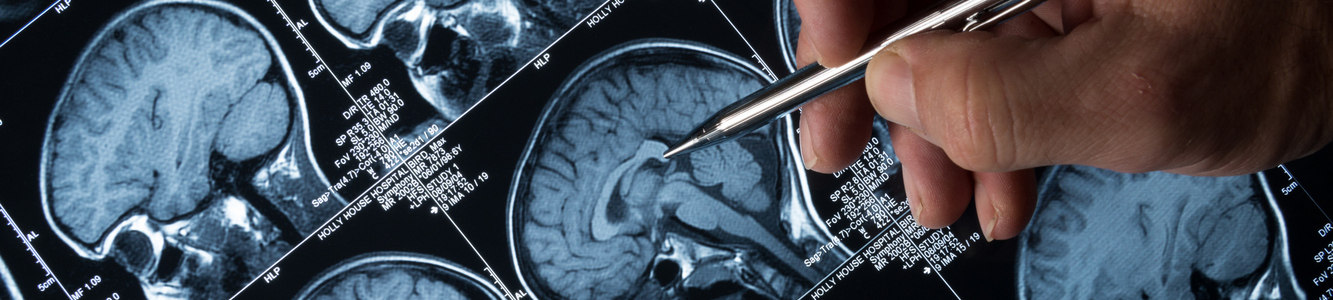

“Es una enfermedad cerebral crónica”  no contagiosa, caracterizada por una predisposición a presentar crisis epilépticas espontáneas y recurrentes. Estas se producen por descargas eléctricas anormales de las neuronas de la corteza cerebral.

¿Sabías que “hasta el 10% de las personas de todo el mundo tiene una crisis epiléptica a lo largo de la vida”? Sin embargo, tener una crisis no quiere decir que uno padezca epilepsia. Hablamos de epilepsia cuando se presentan 2 o más crisis epilépticas no provocadas o cuando un paciente ha presentado solo una crisis epiléptica y tiene un electroencefalograma que muestra actividad epileptiforme o una neuroimagen en que se observe una lesión que explique las crisis. Dado que en estos casos el riesgo de presentar una nueva crisis epiléptica a futuro es mayor del 70% se habla de epilepsia.